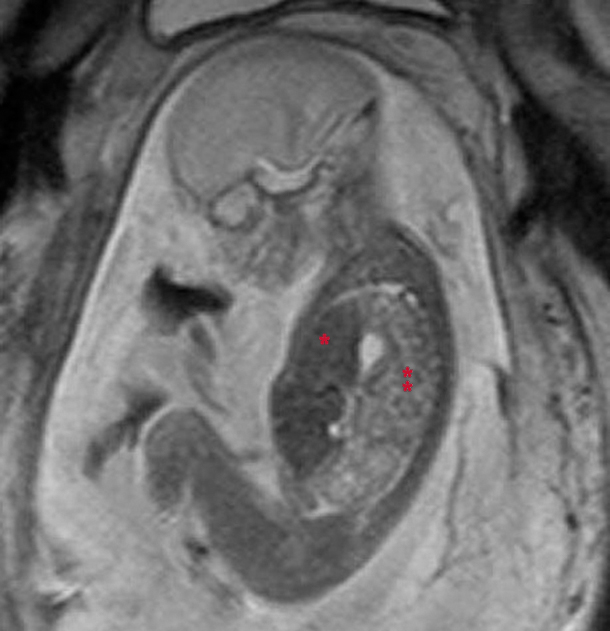

| Fetal MRI of 21-week fetus with congenital diaphragmatic hernia, showing abnormal liver (*) and bowel (**) in chest. (Click to enlarge.) |

Conditions now treated with prenatal surgery include airway and lung malformations, diaphragmatic hernia, twin-to-twin transfusion syndrome, select heart defects, spina bifida, and unique tumors, among others.

Prenatal ultrasound is routinely used as initial fetal survey imaging which oftentimes may identify a worrisome fetal anomaly. Fetal MRI is often used to better clarify or define the anomaly in question.